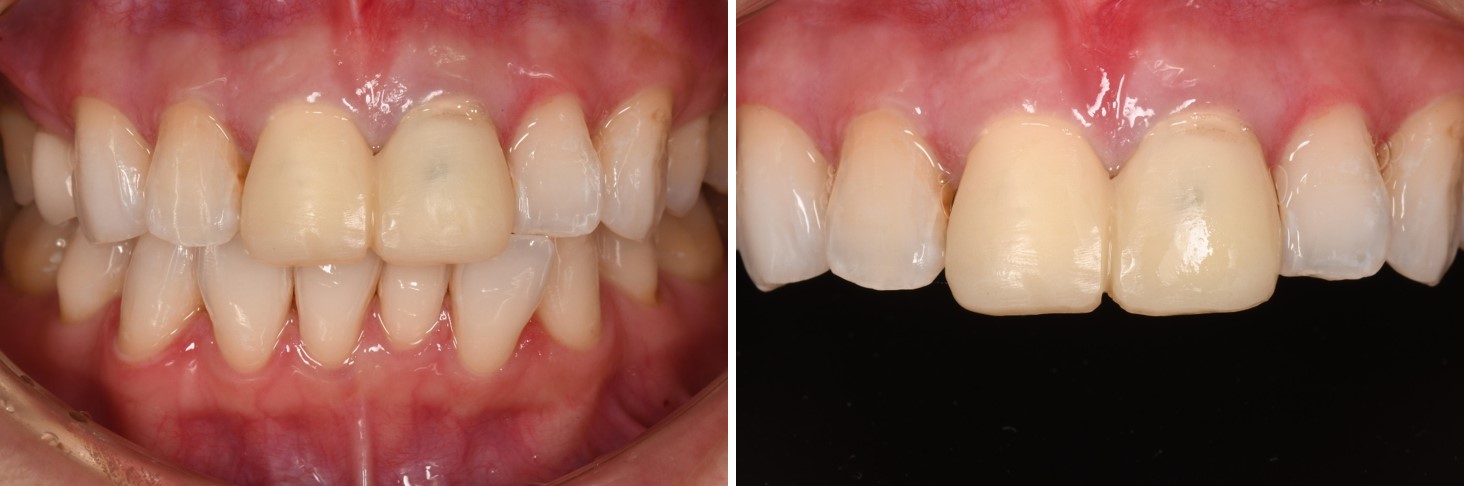

初診口內照,前牙美觀不良

術前、術後比較